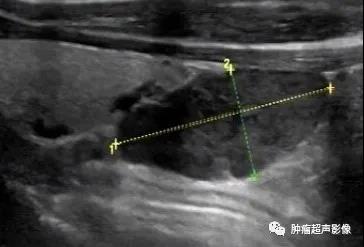

病理证实的甲状旁腺腺瘤:位于甲状腺下极旁,完整的包膜,呈低回声,血流丰富且为典型的极性血供,由一端进入后呈分支分布,符合典型的甲状旁腺腺瘤。